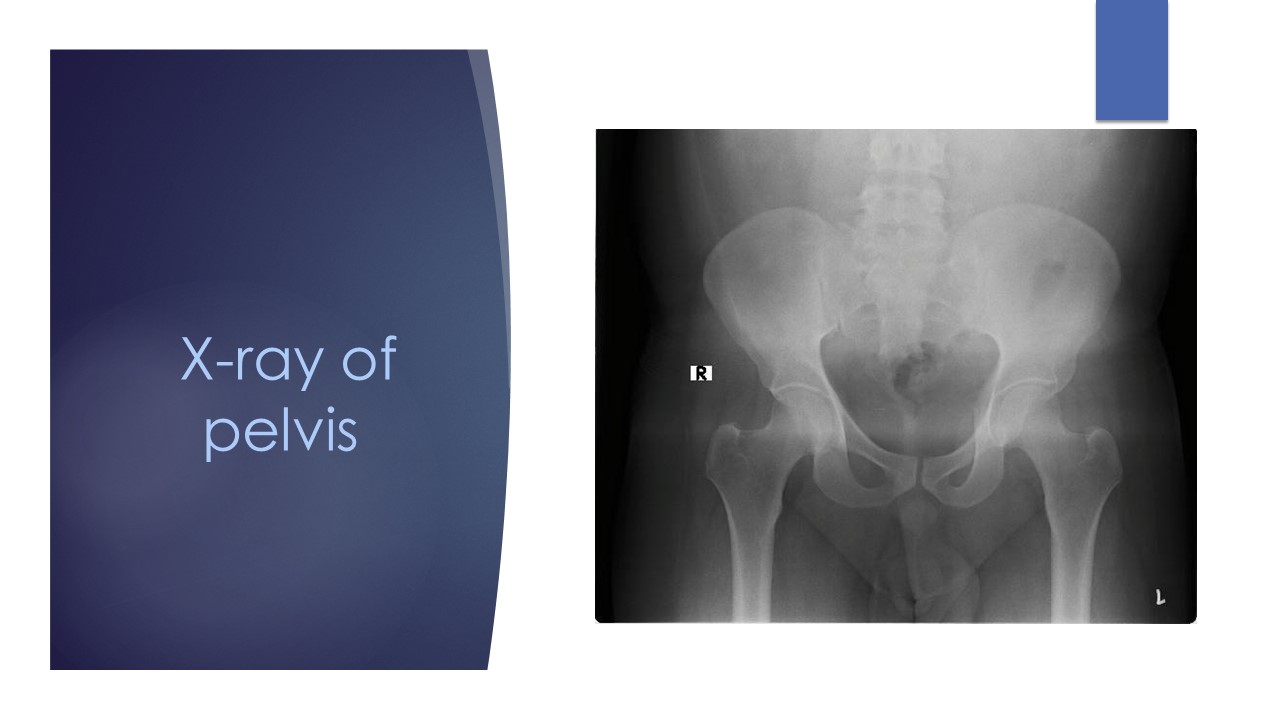

The middle-aged male patient had a 6-month history of symmetric arthritis (predominantly involving the lower limb), inflammatory back pain, episodes of recurrent diarrhea, and one previous hospital admission for diarrhea, which led to reactive arthritis. He had other systemic features like fever and vague abdominal discomfort. His inflammatory parameters were significantly elevated, though the rheumatoid factor and ANA were negative. Chest X-ray was normal and pelvis AP view indicated bilateral sacroiliitis.